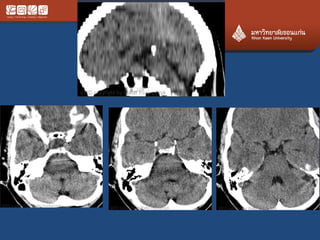

# chordoma

• Locally agreesive never metas

• Clivus, upper C, lower L, sacrum

• 70% at the midline

• Expansile, calcification, bright T2

• Ddx chondrosarcoma